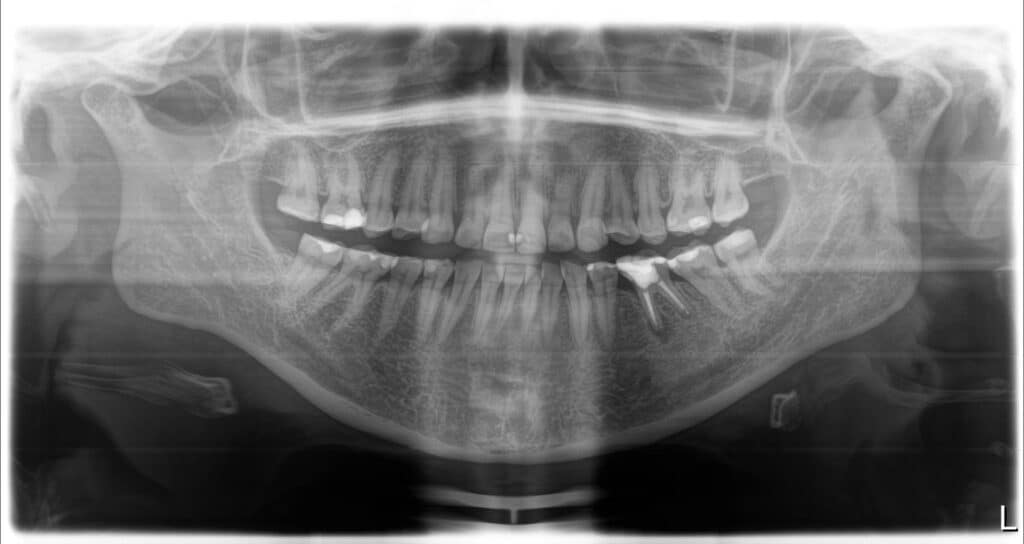

der Zahnsubstanz erhalten hatte, hatte sie kaum getragen. In der aktuellen Situation hatte die Patientin keine Schmerzen, war aber mit dem Erscheinungsbild ihres Lächelns sehr unzufrieden. Ihre allgemeine Anamnese war unauffällig. Der klinische Befund bestätigte, dass die Zähne im Ober- und Unterkiefer, besonders die Frontzähne des Oberkiefers, von starken Abrasionen betroffen waren. Darüber hinaus ergab der klinische Befund bei inkomplettem Zahndurchbruch und ske-lettaler Klasse Il zusätzlich Verfärbungen der Zahnsubstanz und Gingiva-Rezessio-nen (Abb. 2 und 3).

Nachdem in der Smilecloud ein Patien-tenfall neu angelegt wurde, konnten alle relevanten Dateien, wie Fotos, Scans und Röntgenbilder, hochgeladen werden. Das Team, das sich mit dem Fall beschäftigen sollte, wurde zusammengestellt, indem ein Koordinator die entsprechenden Personen einlud. Wer Zugang zum Fall hat, entscheidet also der Koordina-tor. Die Personen, die zum Team gehö-ren, können dabei in unterschiedlichen Teilen der Welt sein. Sie befinden sich im selben Behandlungsraum (Virtual Treat-ment Room). Informationen oder Anweisungen werden direkt in einen Chat ge-sendet. Das gewährleistet eine schnelle und präzise Kommunikation.